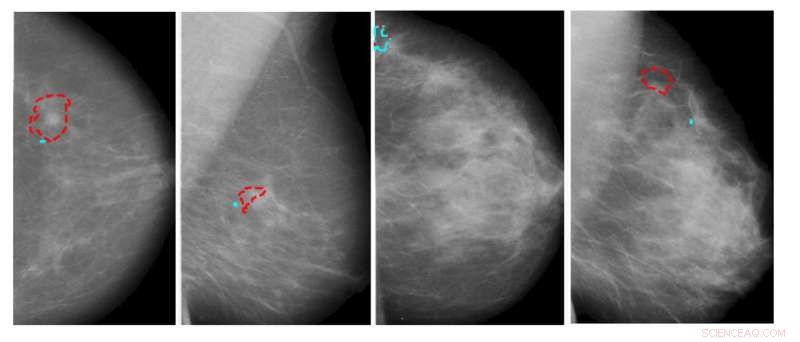

In these examples of lesion detection, red contours denote automatically detected pairs that correspond to ground truth; cyan contours are false positive automatic detections that were reduced by the dual-view algorithm. Credit: IBM

Scientists from IBM Research-Haifa in Israel developed a specialized deep neural network designed for mass detection and localization in breast mammography and will present their findings at MICCAI's 4th Breast Image Analysis Workshop.

Standard breast cancer screening involves taking two mammography X-ray projections for each breast and comparing the views to pinpoint areas of interest. The new network's design included identical "Siamese" subnetworks, from which analyses were compared to produce image evaluations. The study suggested an effective way of training AI to flag areas of abnormal and potentially cancerous breast tissue.